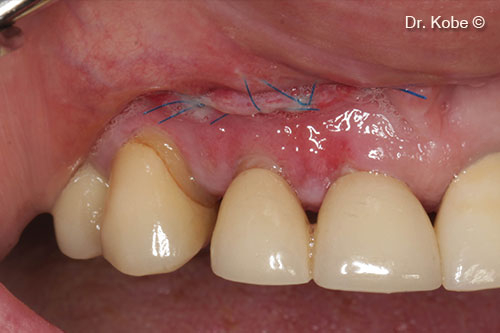

Wound sutured with interrupted sutures